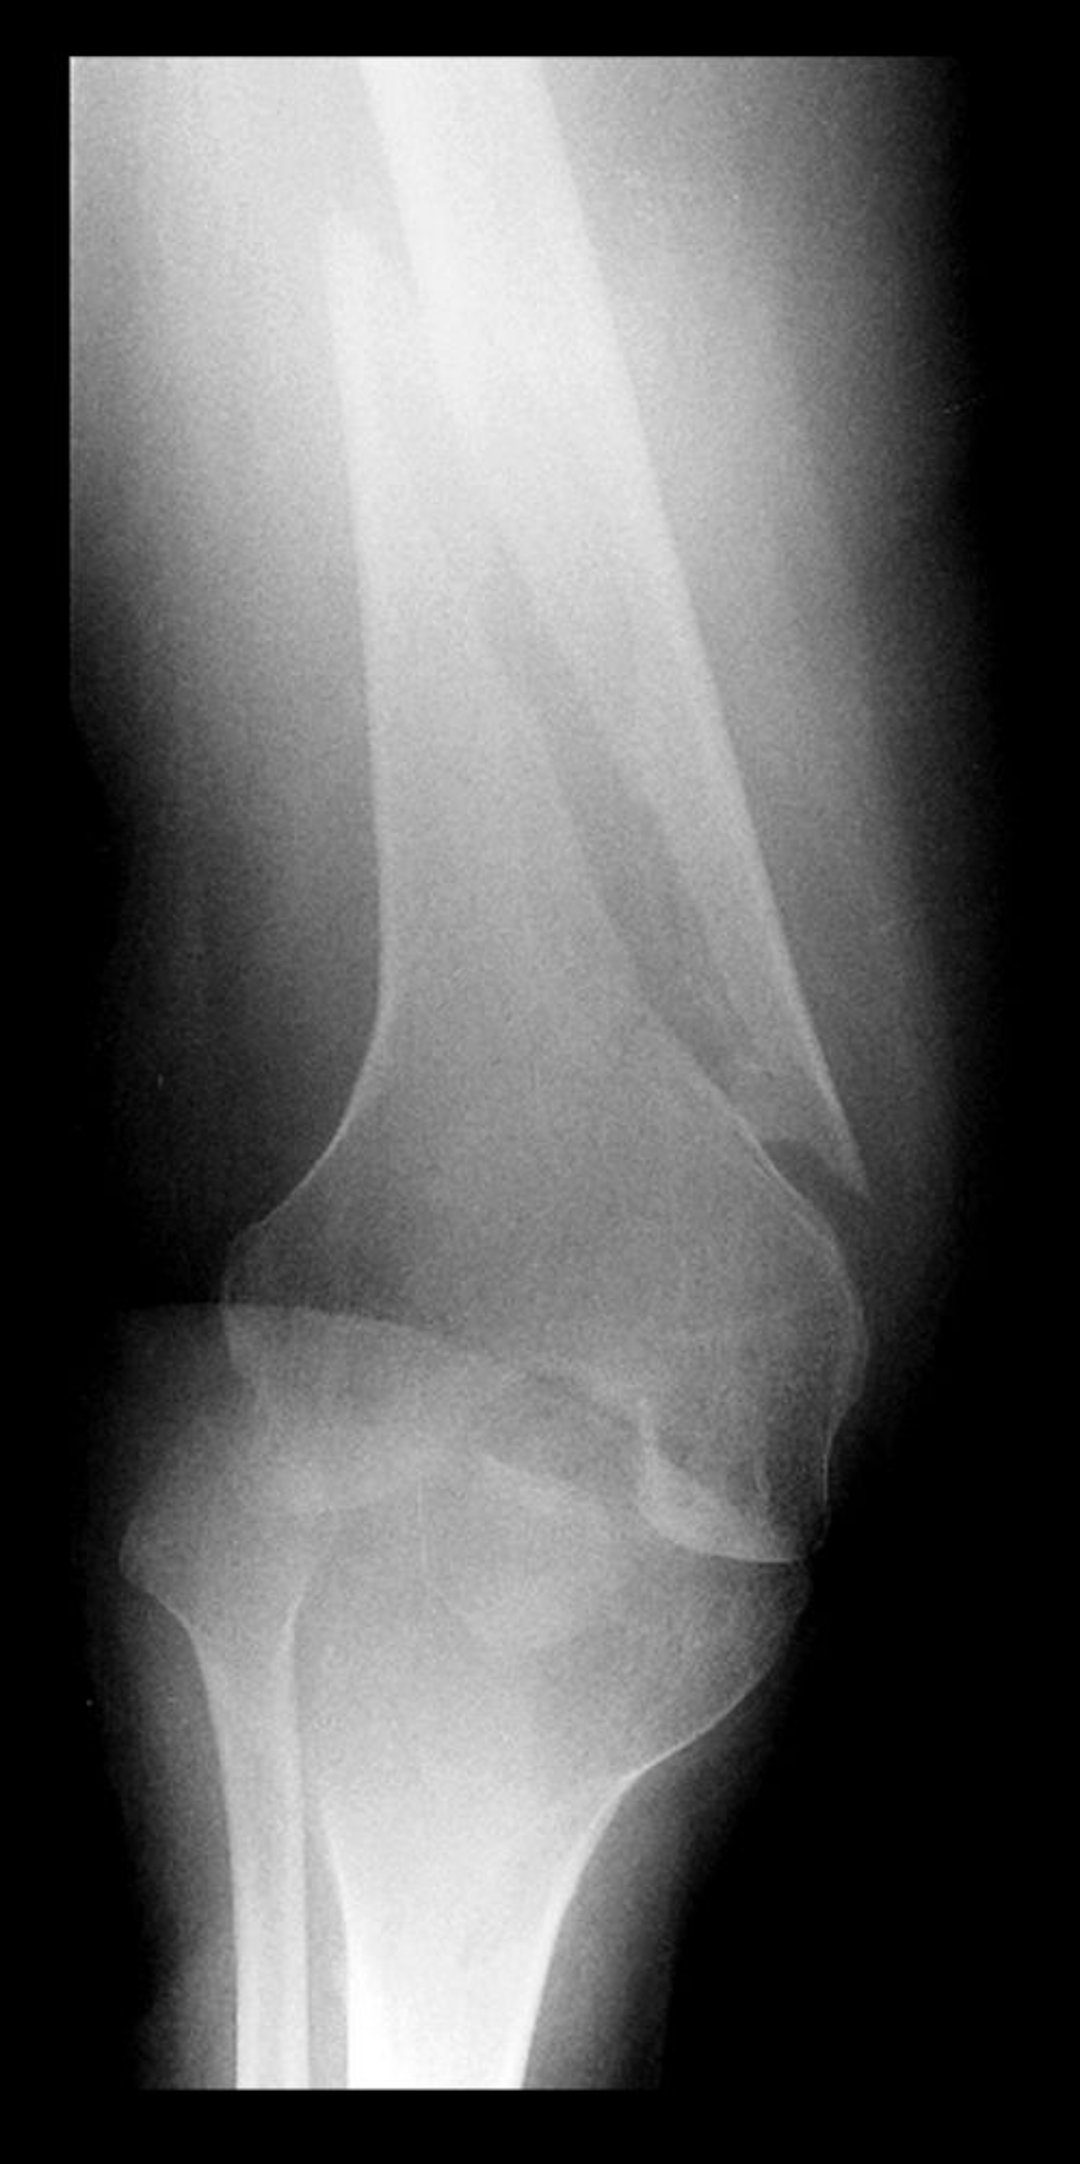

Fractura vertebral en el fémur distal

Esta radiografía del fémur distal muestra radiolucidez con un componente paralelo al eje longitudinal del hueso, lo que indica una fractura en espiral.